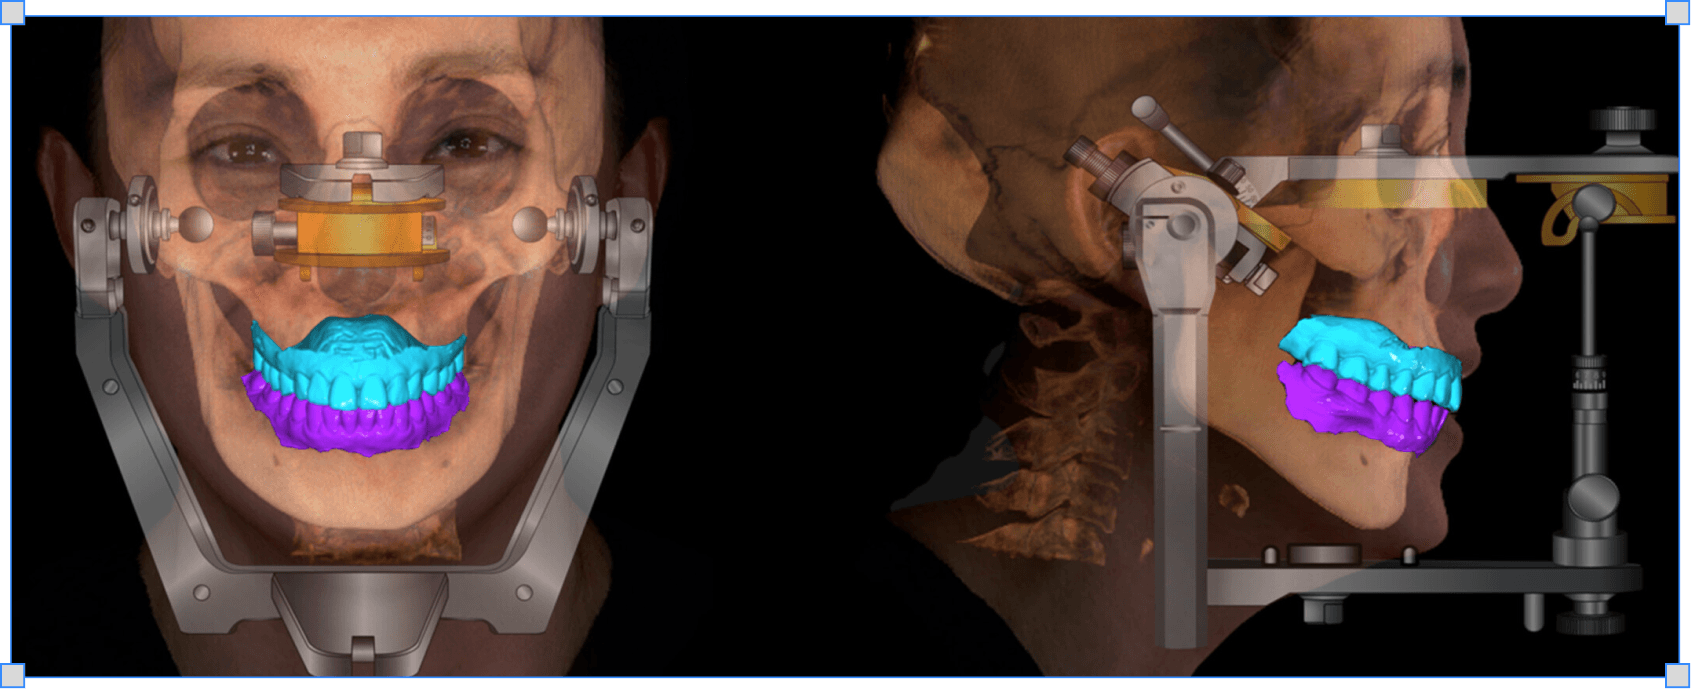

Ознаки бруксизму і дисфункції СНЩС, пальпація і міографія, воскова реєстрація щоб реставрація не дестабілізувала суглоб

Як знаходити центральне співвідношення

Чому звичне змикання і центральне співвідношення різні і як знайти повторювану позицію суглобу

→ Знаходиш повторювану позицію суглобової голівки для реєстрації

Як реєструвати центральне співвідношення

Яким воском і як робити реєстрацію щоб технік загіпсував моделі точно в центральному положенні

→ Технік гіпсує моделі в центральному співвідношенні без здогадок